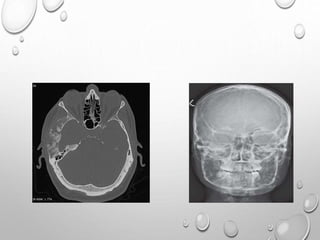

ACHONDROPLASIA

FAILURE OF NORMAL ENCHONDRAL CARTILAGE GROWTH AT

PHYSIS

PERIOSTEAL , MEMBRANOUS OSSIFICATION ARE NORMAL

• MOST COMMON TYPE OF DWARFISM

• AUTOSOMAL DOMINANT DISORDER AND THE MAJORITY OF

CASES (75-80%) ARE THE RESULT OF A NEW (DE NOVO)

MUTATION , ASSOCIATED WITH AN INCREASE IN PATERNAL

RADIOLOGY

HEAD

LARGE CRANIUM , THOUGH DECREASED AP DIAMETER –

BRACHYCEPHALY

NARROW FORAMEN MAGNUM

SHORT BASE OF SKULL

BASILAR IMPRESSION

FACE

FRONTAL BOSSING

DEPRESSED NASAL BRIDGE

NORMAL MANDIBLE ,SO IMPRESSION OF PROGNATHISM

CONSIDERING THE INCIDENCE AND POTENTIAL SEVERITY OF NEUROLOGIC

SYMPTOMS ASSOCIATED WITH FORAMEN MAGNUM STENOSIS, A BASELINE MRI

IS STRONGLY RECOMMENDED IN INFANCY.

MRI SHOWING CERVICOMEDULLARY COMPRESSION AT FORAMEN MAGNUM